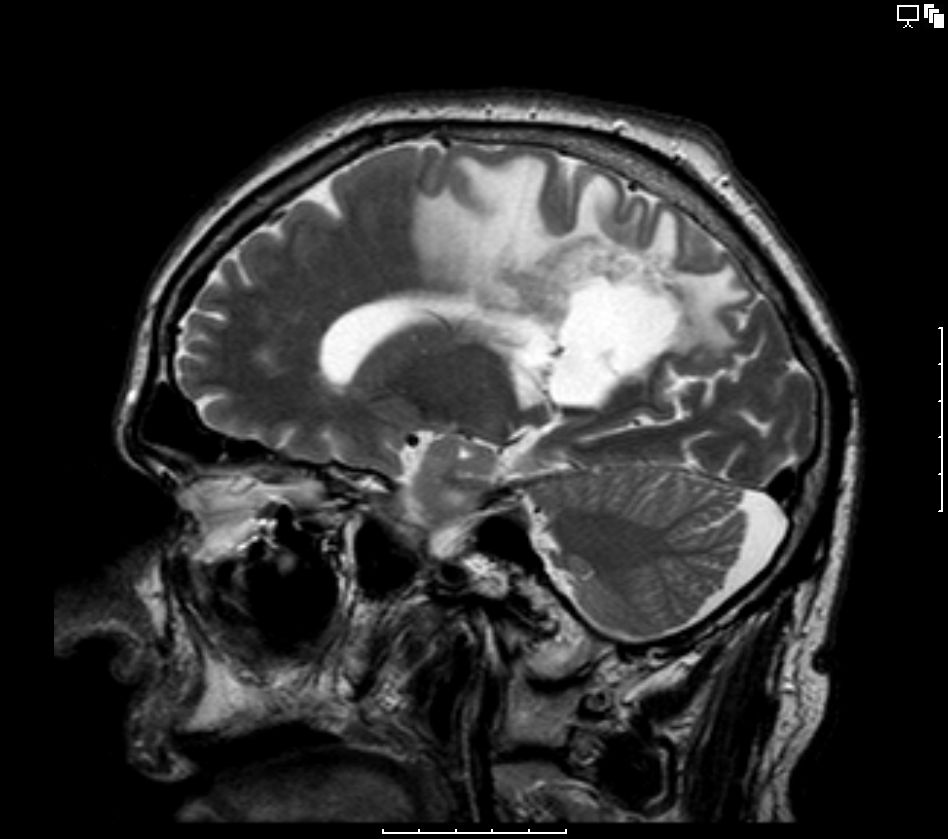

64-jährige Frau mir generalisierten Krampfanfällen und Hemiparese links.![]() | ||||

MRT |